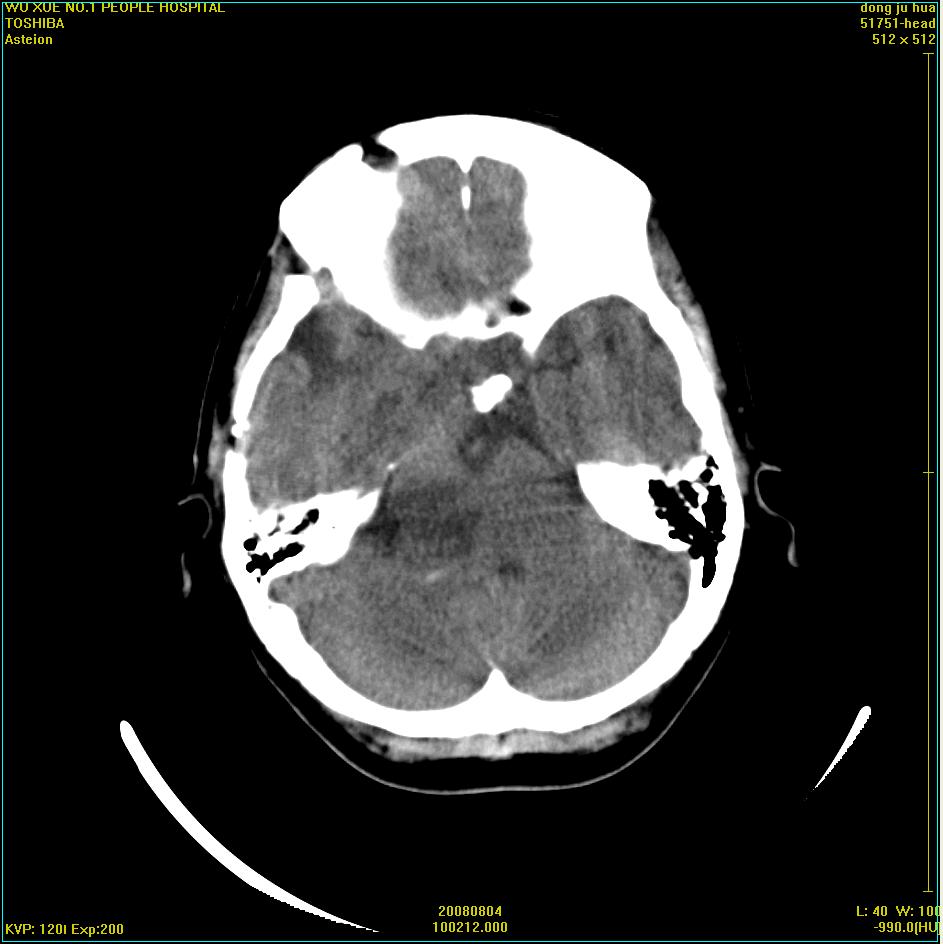

标题: CT15022:女,45岁。右侧桥小脑脚区三叉神经鞘膜瘤,已做手 [打印本页]

标题: CT15022:女,45岁。右侧桥小脑脚区三叉神经鞘膜瘤,已做手

患者,女,45岁。四年前在我院做ct诊断为右侧桥小脑脚区三叉神经鞘膜瘤,已做手术。今复杳。请大家看看

考虑三叉神经鞘膜瘤术后复发并瘤体内出血。

三叉神经鞘膜瘤术后复发并瘤体内出血

考虑慢性扩张性血肿吧!请大家再看看,发表高见!